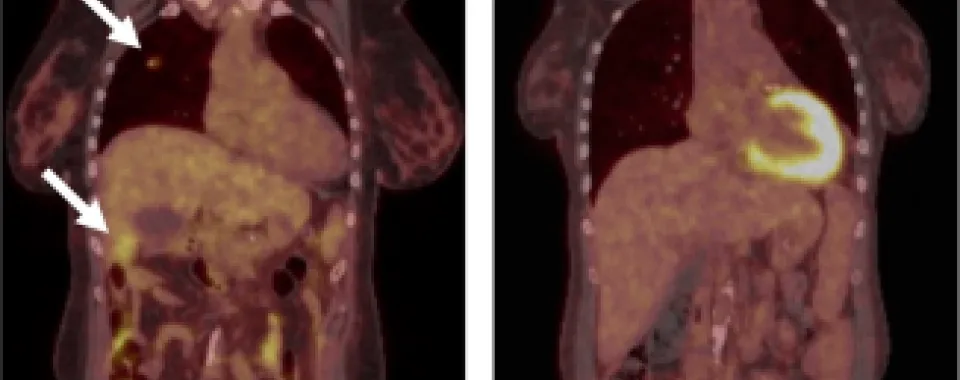

Légende de l'illustration: PET-CT-scanner montrant la tumeur du rein avec les métastases hépatiques et pulmonaires (gauche, flèches). PET-CT-scanner après la disparition complète des tumeurs à 6 mois (droite).

Durant trois mois, la patiente a supporté le traitement et ses effets secondaires, pour que six mois plus tard, il ne reste plus aucune trace de la tumeur et de ses métastases. «Ne pouvant plus prendre ses médicaments anti-rejet, cela a eu un impact irréversible sur les organes greffés et la patiente a dû reprendre ses dialyses. Mais aujourd’hui, sept ans plus tard, il n’y a plus aucune trace de ce cancer agressif, alors qu’elle semblait condamnée, et une nouvelle greffe pourrait être envisagée», se réjouit Raphaël Meier.